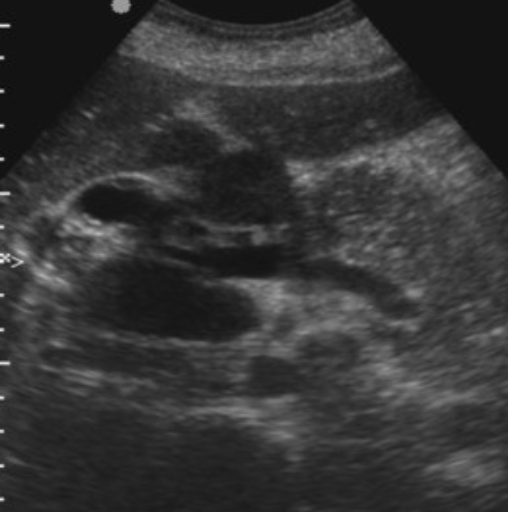

Complex Renal Cyst → any cyst that is not a simple cyst

clinical hx: post-surgery, trauma

s/sx: flank pain, fever, hematuria, WBC increase, can be asymptomatic

2D US: well-defined cystic structure, internal echoes or anechoic, septations, focal hypoechoic inner mural extension, can be hemorrhagic

color doppler: if solid can have vascularity

DDX: malignant tumor, RCC